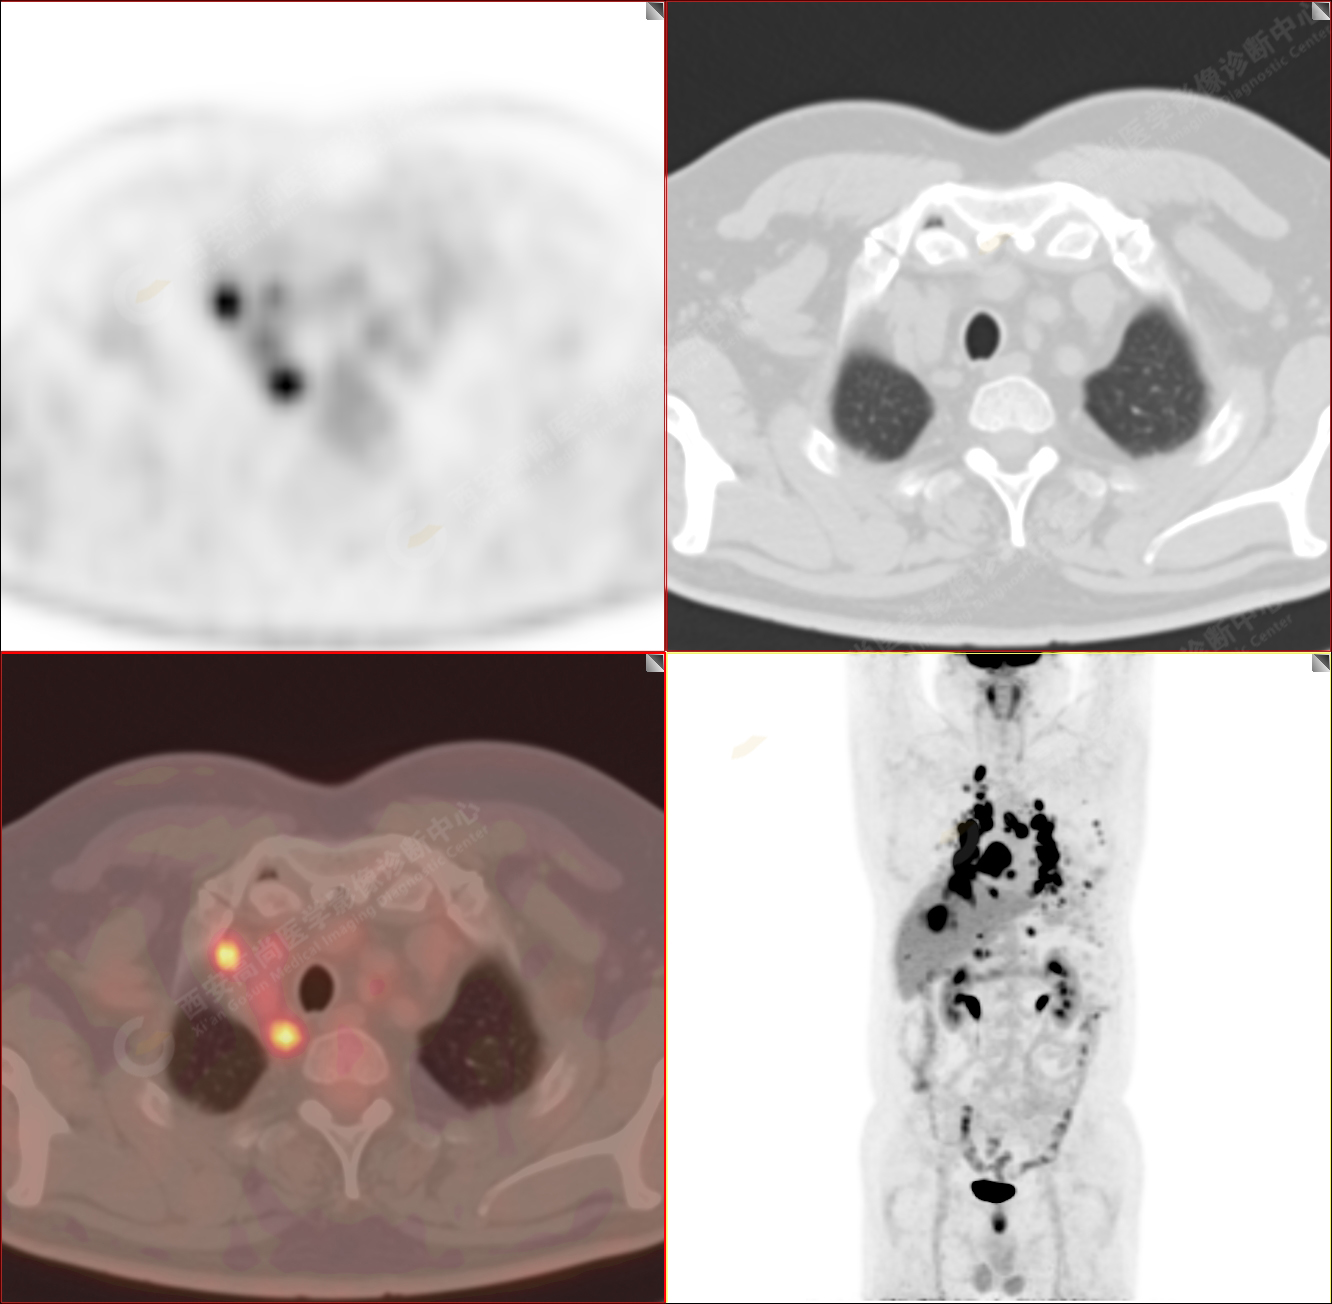

男性,53歲,頭暈半月入院,CT發(fā)現(xiàn)肺內(nèi)腫塊,雙肺多發(fā)大小不等實性及粟粒樣結(jié)節(jié),雙肺門及縱隔多發(fā)腫大淋巴結(jié)。病程中無發(fā)熱、胸悶氣及胸部不適。既往:左側(cè)肋骨外傷史。

PET/CT圖像